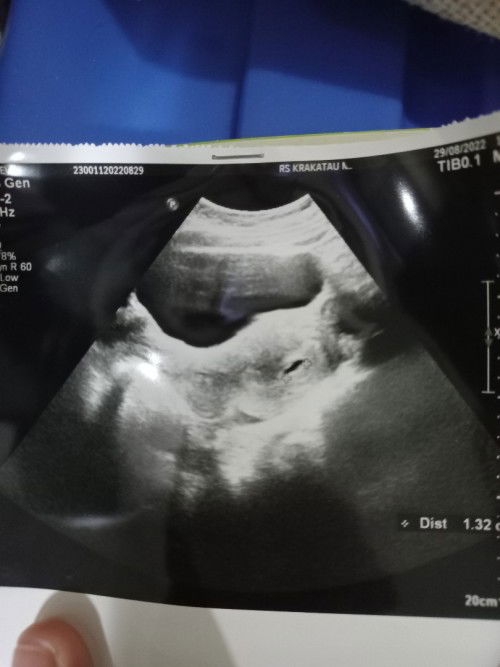

USG 6week, dgn Hpht 15Juli ada yg sama?

Haloo bund , apakah dsni ada yg sama kaya aku dgn Hpht 15juli Di usg tgl 29Agustus baru terlihat kantung?#bantusharing